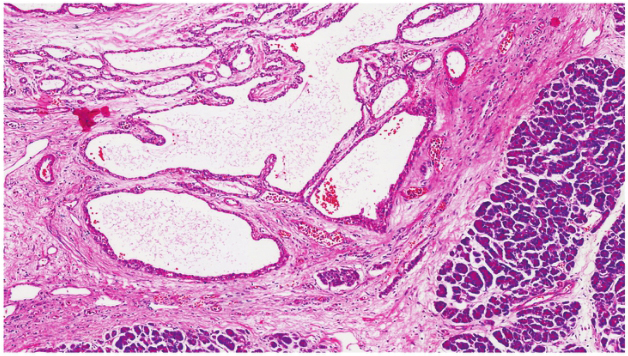

送检胰十二指肠切除术标本,胰头部可见一肿块,大小6.5cm×5cm×6cm,切面灰白灰黄,略呈囊性,内充清亮液。镜下示:大量小囊组成,囊壁被覆单层立方或扁平上皮,胞质透亮,细胞分界清晰,核深染,大小较一致,与上皮紧邻处可见明显的毛细血管网,囊腔周围为明显玻璃样变的纤维组织(图4)。本例形态典型,诊断明确为胰腺微囊型SCN。

图4 肿瘤切片HE染色(×100)

多个囊腔内衬透明的立方上皮,可见呈乳头状突向腔内,肿瘤与周围的胰腺组织分界不清。